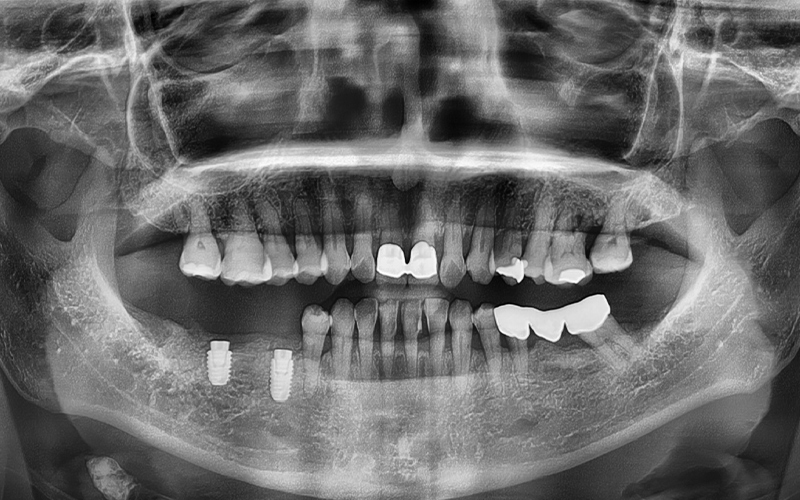

최종적으로 크라운(보철물)까지 올려

치료를 성공적으로 마무리 해드렸답니다!

💕 전 > 후 💕

2025.02.13 ㅡ> 2025.06.11

이렇게 사랑니발치 및

임플란트 치료 사례를 소개해드렸는데요.